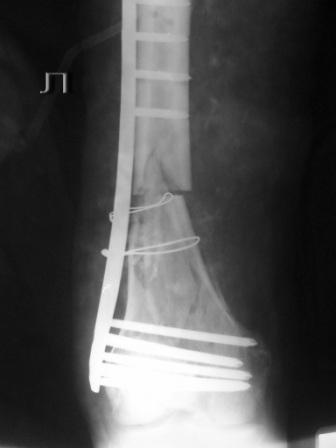

Оставлен клинически значимый варус, видно градусов 8-10. Для уточнения можно сделать снимок симметричного сегмента и скиаграммы наложить.

Не стоило открывать промежуточные отломки и вязать их проволокой. Это ухудшает их кровоснабжение и может привести к несращению. Не во все случаях, конечно. Удачи.

Сложность репозиции привела к "освобождению" промежуточных отломков - появился значительный костный дефект - пришлось создавать картинку + добавили коллапан.

В Вашем примере, как мне кажется, была довольно травматичная открытая реползиция со скелетированием концов перелома. В результате отсутствует необходимая биологическая составляющая для нормальной репарации кости. кроме того, положение отломков по оси - так себе, и имеется значимый медиалный дефект. Так что к био-логической мостовидной технике фиксации переломов этот случай не имеет никакого отношения. Увы(